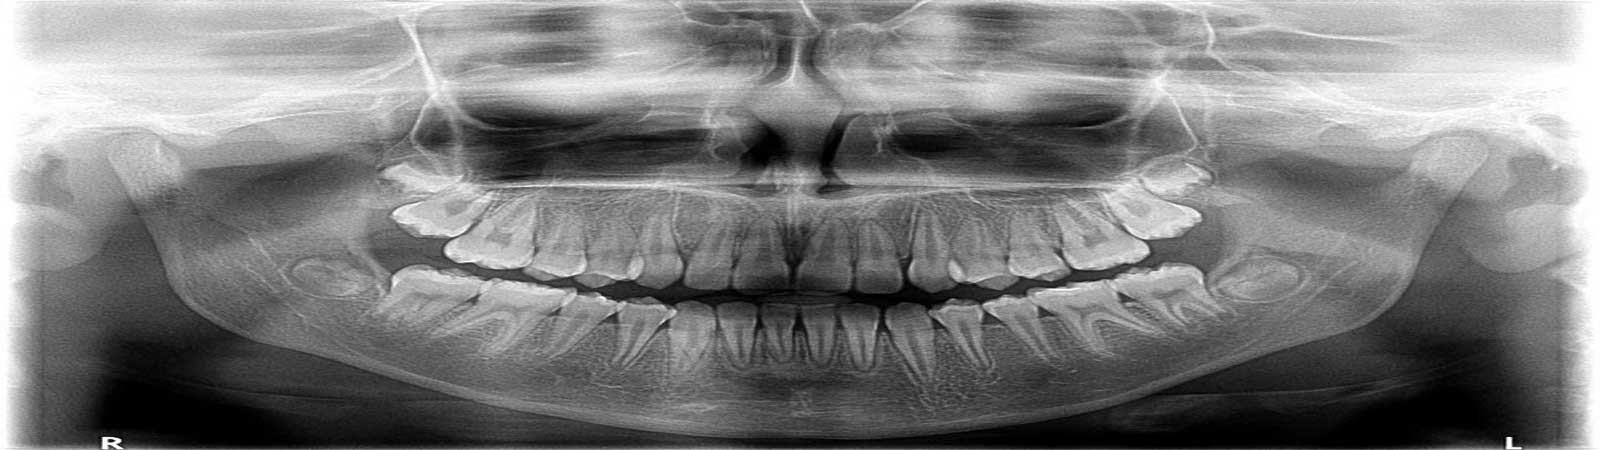

RVG(دستگاه رادیوگرافی دیجیتالی مدرن) : این نوع رادیوگرافی بسیار پیشرفته قابلیت عکسبرداری را به صورت دیجیتالی و با یک دهم میزان اشعه دارا می باشد.

تصاویری شفاف و دقیق در کمتر از 3 ثانیه بر روی کامپیوتر آماده و قابل چاپ می باشد و نیازی به کلیشه های قدیمی نیست. سیستم نرم افزاری بسیار پیشرفته و قوی با دسترسی آسان به تمام ابزارهای موردنیاز جهت هر گونه تغییر و تصحیح، امکان آنالیز تصاویر را در بزرگنمایی مناسب و دلخواه در اختیار دندانپزشک قرار می دهد. سیستم مونیتورینگ تمامی رادیوگرافی ها به صورت شبکه بر روی یونیت های کلینیک نصب شده و دسترسی به آن از تمامی مونیتورها امکان پذیر است. علاوه بر آن امکان داشتن کپی در آرشیو از تمامی فایل های ایجاد شده به صورت دیجیتالی بر روی کامپیوتر و همین طور نسخه چاپ شده آن وجود دارد. طراحی ویژه این دستگاه باعث جلوگیری از بروز آسیب به دهان بیمار در هنگام قرار گیری داخل دهان شده و سهولت در پوزیشنینگ را به همراه خواهد داشت.

رادیوویزیوگرافی دیجیتال (RVG) جدیدترین فناوری پرتوی ایکس در دندانپزشکی است. رادیوویزیوگرافی دیجیتال مجهز به نرم افزار آنالیز تصویری ویژه ای است که در آن این امکان فراهم شده است که تصاویر بزرگ شده و آنالیز شود و در پرونده بیمار ذخیره گردد. برخی از مزایای رادیوویزیوگرافی دیجیتال عبارتند از:

•  کاهش 80 درصدی تشعشع بیمار در مقایسه با تصاویر پرتوی ایکس سابق

• تصویر برداری سریعتر بدون فیلم پرتوی ایکس و تولید تصاویر

• حسگر دیجیتالی داخل دهانی که به جای فیلم پرتوی ایکس استفاده میشود

• ایجاد تصویر فوری در نمایشگر کامپیوتر

• کیفیت بالای تصاویر دیجیتال که میتوان آن را آنالیز و پردازش کرد

• ذخیره سازی تصاویر در پرونده بیمار

• در صورت نیاز به تصویر برداری به علت کاهش تشعشع، برای کودکان اشکالی ایجاد نمیکند